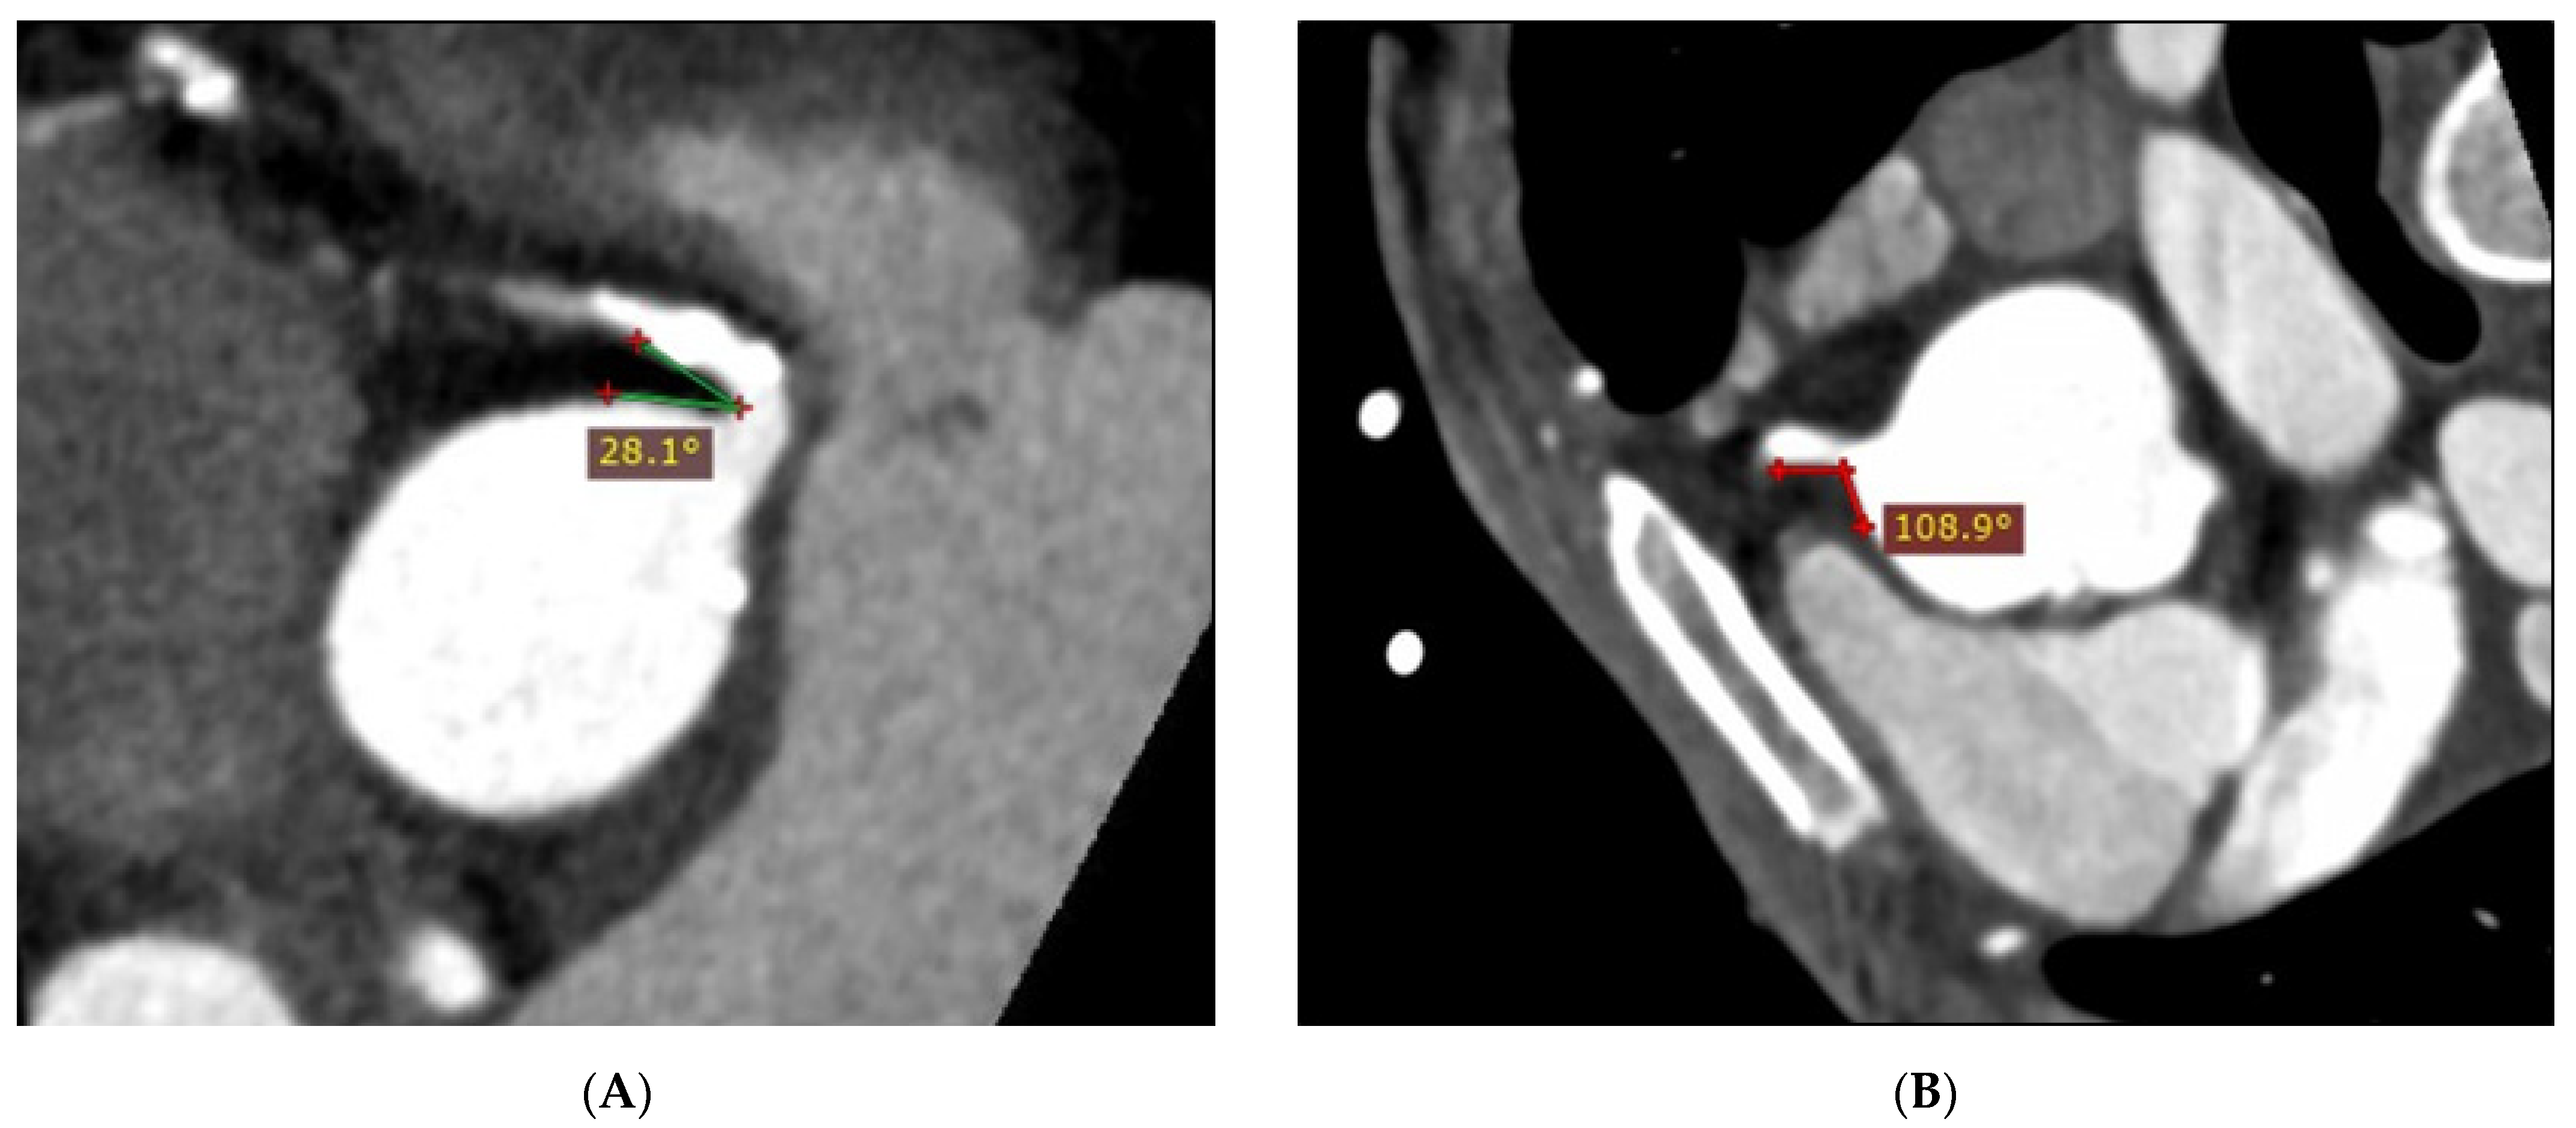

2.3. Coronary Angle Measurement